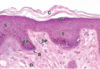

Name a few histologic appearances of the stratum basale.

Closely spaced nuclei

Basophilic

Melanin

(Note: B in image)

Describe the appearance of the stratum spinosum.

What cell junction is present in both the stratum spinosum and basale?

Larger and flatter cells than in the stratum basale;

desmosomes

(Note: the ‘spines’ on the cells are an artifact of slide preparation)